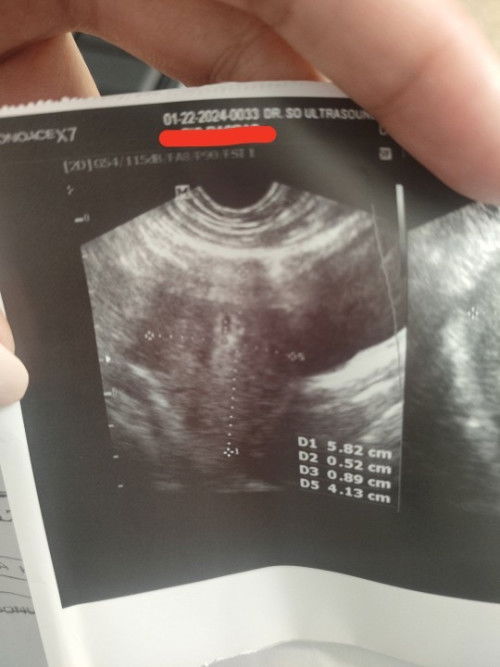

7-8 Weeks Ultrasound

Hello, may nakaranas na po ng ganitong result ng US? Grabe sobrang liit mo ng gestational sac ko for 8 weeks kc nagsearch ako sa mga online platforms at nakikita ko po sa iba na 6 weeks palang malaki na yung bilog na nakikita sa US. I recently had a miscarriage kaso naiwan po yang sac sa loob pero wala pong embryo sa loob as in clear lang sya. Pero bakt po ang liit? 😓

7-8 weeks pregnancy

Nag spotting po ako nung last January 15 so akala ko normal lang sya then nung gabi biglang sumakit puson ko na parang maglalabor, grabe yung cramping habang dinudugo ako. Then nag CR ako, biglang may lumabas na buo buo na dugo at humupa sakit ng puson ko nung nawala yun. Then yesterday nagpunta kami for ultra sound so sabi sa result there is a small gestational sac but no embryonic pole (meron yung sac pero wala yung embryo) niresetahan ako ng gamot na pampakapit since 50/50 dw na magprogress sya into pregnancy so naguguluhan ako. Kung wala naman embryo bakt need ko pampakapit? Masakit kc umasa na meron tapos wala pala